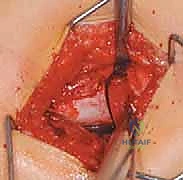

2. الشق الجراحي (The Incision)

يُجري الدكتور هطيف شقاً جراحياً دقيقاً في الجانب الخارجي للفخذ (Lateral Approach). يتميز هذا المدخل بأنه آمن ويحافظ على العضلات الحيوية، وهو ما يعكس خبرة الدكتور في تقنيات الجراحة طفيفة التوغل.

3. إدخال سلك الدليل (Guide Wire Placement)

هذه هي الخطوة الأكثر أهمية. باستخدام الأشعة المباشرة، يقوم الدكتور بإدخال سلك معدني رفيع في عنق عظم الفخذ باتجاه الرأس. يتم وضع هذا السلك بزاوية محسوبة مسبقاً بدقة متناهية لتتطابق مع زاوية الشريحة (90 درجة).

4. تحضير مسار الشريحة النصلية (Seating Chisel)

باستخدام أداة خاصة تشبه الإزميل، يتم حفر مسار دقيق داخل العظم الإسفنجي لعنق الفخذ، وذلك تمهيداً لإدخال نصل الشريحة المعدنية.

5. قطع العظم (The Osteotomy)

باستخدام منشار جراحي عالي الدقة، يقوم الدكتور هطيف بقطع عظم الفخذ أسفل منطقة المدور الكبير (Subtrochanteric). في هذه المرحلة، يتم إزالة إسفين عظمي صغير (Wedge) بالزاوية المطلوبة لتصحيح التشوه.

6. إدخال الشريحة والتثبيت (Plate Insertion & Fixation)

يتم إدخال نصل الشريحة ذات الزاوية 90 درجة في المسار الذي تم تحضيره في عنق الفخذ. ثم يتم ضم جزئي العظم المقطوعين معاً (إغلاق الفجوة)، مما يؤدي فوراً إلى تغيير زاوية عنق الفخذ إلى الوضع الطبيعي الجديد. يتم تثبيت الجزء الطويل من الشريحة على جسم عظم الفخذ باستخدام براغي قوية من التيتانيوم أو الفولاذ الطبي المقاوم للصدأ.

7. الإغلاق التجميلي

بعد التأكد من صلابة التثبيت ووضعية المفصل المثالية عبر الأشعة، يتم غسل الجرح وإغلاقه بطبقات متعددة باستخدام خيوط تجميلية لتقليل الندبات.